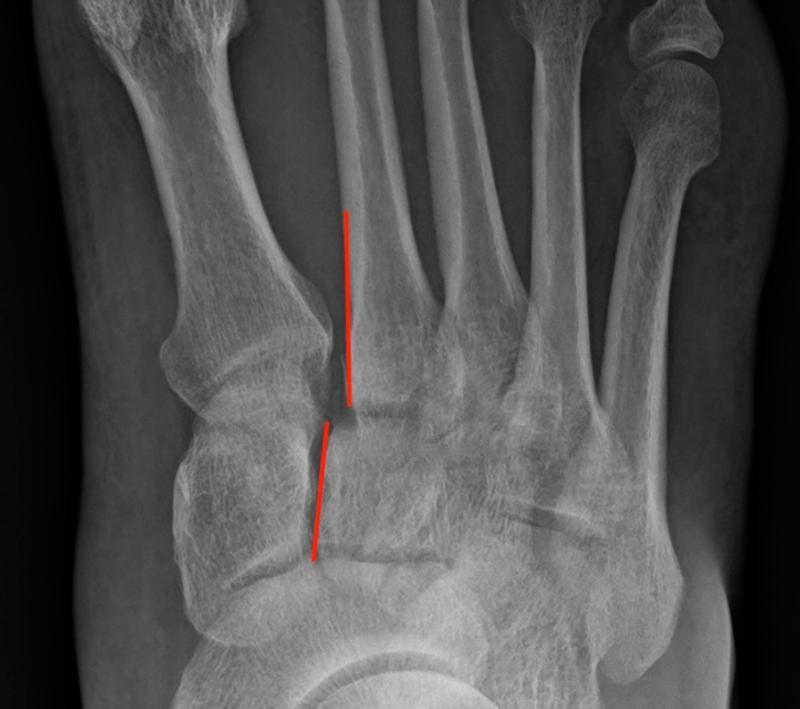

The weight-bearing acts as a stress which can reveal an occult Lisfranc injury. On a normal weight-bearing X-ray the medial border of the 2nd metatarsal lines up with the medial border of the intermediate cuneiform. The base of the 2nd metatarsal is recessed between the medial cuneiform and 3rd metatarsal. It is held in place by three oblique ligaments between the medial cuneiform and 2nd metatarsal. The central interosseous Lisfranc ligament is the strongest, followed by the plantar ligament and the weaker dorsal ligament. There is no intermetatarsal ligament between the 1st and 2nd metatarsals. A normal DP X-ray shows alignment of medial border of the 2nd metatarsal with the medial border of the intermediate cuneiform. A normal oblique X-ray shows alignment of the medial border of the 4th metatarsal with the medial border of the cuboid. If either of these views shows subluxation of the metatarsal base, usually laterally, that indicates a Lisfranc injury (Figure 2). The key is usually the alignment of the base of the 2nd metatarsal and other indicators can be a fleck sign between the base of the 1st and 2nd metatarsal, indicating a bony avulsion (Figure 3), and diastasis between the 1st and 2nd metatarsal, the M1-M2 gap, of >2mm.

Fig 2.jpg

Figure 2: 2nd metatarsal base is subluxed laterally.